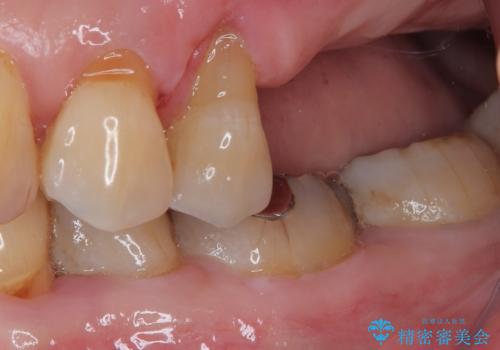

骨量の少ない上顎大臼歯 骨補填材を用いない短期間インプラント治療

元々の骨量が少なく、通常よりは待機期間が長くなりますが、数ヶ月程度で補綴治療まで行うことができるため、こちらの手法でインプラント補綴治療を行うこととしました。

インプラントが待機期間に脱落することがありますが、一切のトラブルなく、最短期間で無事に治療を終えることができました。